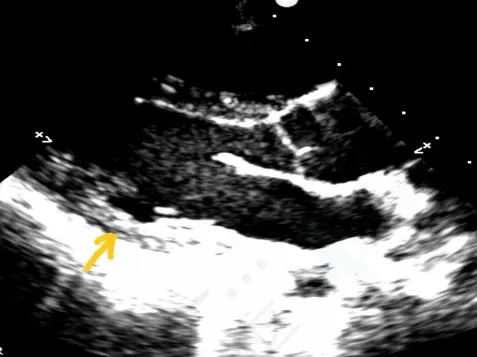

门诊心脏彩超提示:

超声多切面示:室间隔膜周部可见连续中断,局部不规则向右室膨出,呈“囊袋状”,断端回声增强,测缺口大小:左室面6.5mm、右室面2.5mm,隔瓣下残缘5mm,彩色血流示:室水平左向右分流,Vmax 473cm/s,Pgmax 89 mmHg。

各房室腔大小及大血管内径未见异常。各瓣膜厚度、弹性、开放幅度正常,彩色血流示:三尖瓣反流(少量),长度1.51cm、面积1.4cm2,容积1.0ml,Vmax 216cm/s,PGmax 16mmHg。据三尖瓣反流法估测肺动脉收缩压为28 mmHg;左室收缩功能正常,EF为74%。

术前超声与DSA复测

VSD(膜周部):室间隔膜部瘤,左室面6.5mm,右室面呈“瘤样”结构,瘤体深度7mm,出口2mm。

该病灶呈现为“长隧道、大瘤底、小出口”的细腰形态,且位置紧邻主动脉瓣与三尖瓣,解剖结构较为复杂。此形态特征使得可降解封堵器在植入过程中的定位与释放面临较大挑战。